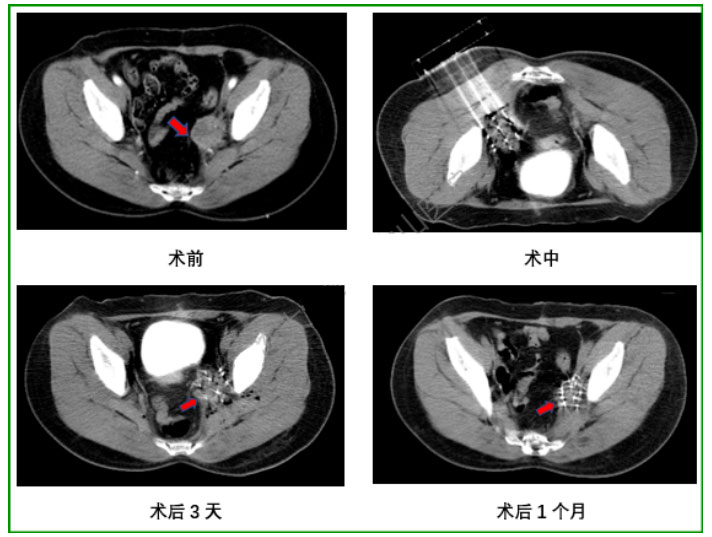

医生:首先要做术前增强CT做计划,确定需要放置的粒子数量、活度、以及穿刺路径和针数。然后手术中需要全身麻醉,医生通过CT引导将放射性粒子一颗一颗打入肿瘤内部。术后3天、1、2、3、6个月需要复查CT,确定肿瘤内粒子分布情况及肿瘤缩小情况。

病例2:患者女,40岁,子宫颈癌根治性切除术后,盆腔转移